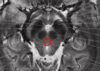

substantia nigra

area in the midbrain involved with movement! assoc with parkinsons disease bc dopamine neurons of SN die.